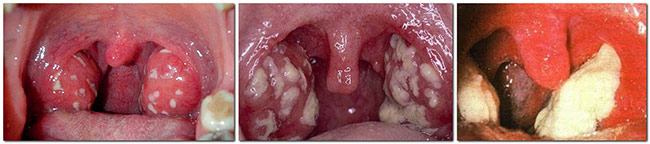

Фолікули запалюються, у них спостерігається скупчення гною. При огляді зіву на цьому етапі його часто порівнюють із «зоряним небом». На гиперемованими тлі видно точкові білі або білувато-жовті высыпные елементи.

Так виглядає фолікулярна ангіна

Фолікулярна. Вражає фолікули гланд. Добре видно скупчення гною, схожі на зернятка просо. Поступово збільшуючись, вогнища закінчуються жовтуватими виділеннями.

піднебінні мигдалини різко збільшені, яскраво гіперемована (тобто почервонілі), набряклі; на їх поверхні є численні округлої форми білувато-жовті або жовті точки. М’яке піднебіння також набряково і гиперемировано.

У міру дозрівання фолікули розкриваються, і гній виходить на поверхню мигдалин, утворюючи плівки біло-жовто-зеленого кольору. Ці плівки легко знімаються шпателем (на відміну від схожих за зовнішнім виглядом плівок при дифтерії) і не залишають після себе кровоточивих дефектів.